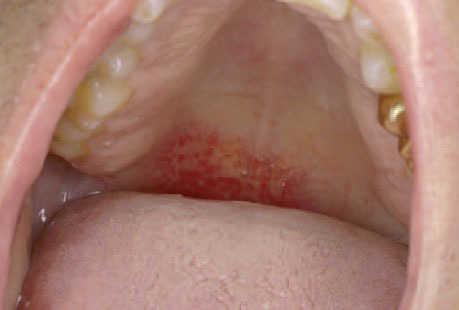

Caso 2Un varón de 60 años, con antecedentes de hipertensión arterial y artritis reumatoide se encontraba en tratamiento con ibersartán, doxazosina, colchicina, omeprazol, prednisona, acenocumarol y metotrexato. El metotrexato se había introducido, junto a la prednisona y la colchicina, hacía 2 meses, en dosis de 5 mg/día, para el tratamiento de la artritis reumatoide. El paciente refería la aparición 10 días antes de acudir a nuestra consulta de unas lesiones maculosas eritematosas en dorso de ambos pies y cara anterior de ambas piernas, así como la aparición de lesiones vesiculosas en tobillo derecho. El cuadro se acompañaba de lesiones erosivas en la mucosa oral de 2 semanas de duración que no respondían al fluconazol. En la exploración física presentaba lesiones maculosas eritematosas purpúricas, confluentes, en la cara interna de las rodillas, los tobillos y el dorso de los pies, y sobre dichas lesiones presentaba alguna lesión vesiculosa. En la mucosa labial inferior y paladar blando existían lesiones erosivas (fig. 3). En la analítica destacaba una hemoglobina de 12,6 g/dl, INR (índice normalizado internacional) de 7,2, creatinina 1,4 y transaminasas mínimamente elevadas.

Fig. 3. Paciente 2 . Lesiones erosivas en paladar blando.